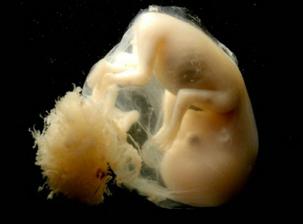

některé obrázky čerpány z http://mimiblog.cz/kt/tyden/1

zázrak lidské života na videu